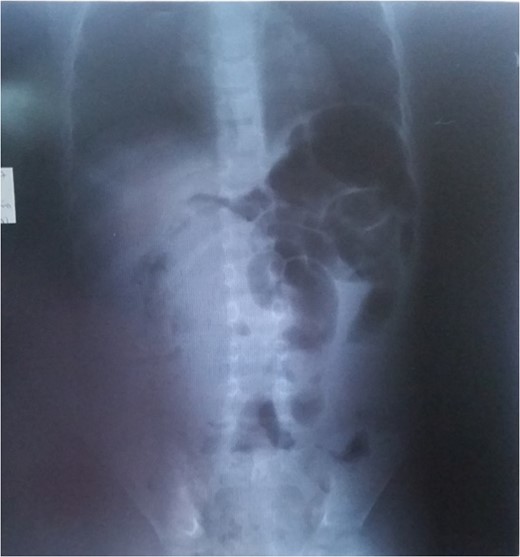

We report the case of a 6-year-old boy who presented at the Emergency Room (ER) of our institution with severe abdominal pain and vomiting. History of presenting complain revealed that one week prior to the consultation, the patient started complaining of intense and progressive pain, initially epigastric but later peri-umbilical. The pain was paroxysmal, without any irradiation and no remitting or exacerbating factor. Three days after the onset of the pain, there was a complete stoppage of stool passage with vomitus which initially was food and later biliary. This prompted the personal administration of Albendazole by the mother but with the persistence of the clinical picture she rapidly brought the child the ER. The past-history was non-contributory. Upon arrival, the patient was anxious, and physical exam revealed a conserved general state, stable vitals, an obstructive syndrome, an irregular umbilical mass, with no abdominal distention and no signs of dehydration. A plain abdominal radiograph revealed an agglutination of distended colonic segments in the left upper quadrant (Fig. 1). An abdominal ultrasound was also conducted and showed a cystic abdominal mass. Complete blood count revealed moderate anaemia. Horizontal laparotomy was done and found a twisted small bowel obstruction with a large encapsulated yellowish mass inserted with a small base on the anti-mesenteric aspect of the ileum measuring 10×15 cm2 at 30 cm away from the ileo-colic junction without any adhesions. On the same insertion but rather on the mesenteric aspect was a smaller greenish mass (3 × 5 cm2) giving a granulated feeling on palpation. There also were numerous lymph nodes on the mesentery. Small bowel bulk resection of 10 cm was done and intestinal end-to-end anastomosis also. Histopathology confirmed the mesentery lipoma and the associated structure to be a myxoma. Post-operative progress notes return of peristalsis and stool from Day 3 post-op (Fig. 2).

Lipomas are common benign tumours developing from mature fat cells. They often are found on the superficial aspects of the body and rarely are they deep-seated [1, 2]. No aetiology for lipomas has been identified but an association with diabetes, raised cholesterol, obesity has been proven [3]. Amongst all the deep locations of lipomas in childhood, the mesenteric location is the rarest (Fig. 1) [4]. The latter is often found in adulthood between 40 and 60 years. Apart from a lipoma, our patient had a myxoma which is extremely rare in this location. They are more common in the heart and originate from mesenchymal tissue. They are benign and when found in the gastrointestinal tract, yields intussusception [5]. Stout [6] reported a series of five cases of intestinal myxomas and of these, himself saw one. The particularity of this case is that it occurs in childhood and does not present with intussusception as described by authors like Varsamis et al., who report this finding to be more common in middle-aged women and present with intussusception [5–7]